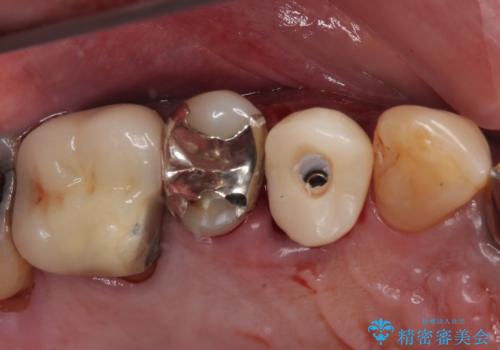

- 抜歯が必要なのでは?と近医で言われ、歯の保存を希望して来院された患者様です。

既に別の部位にインプラント治療を受けており、そのときの治療期間と苦労を鑑みて、何とか歯を残したいとのことで来院されました。

該当歯の状態としては何とか保存可能でしたが、予後不良のため、将来的にインプラント治療が必要となる可能性の高い状態でした。

当院での根管治療および歯周外科治療を併用した保存療法、並びに1DAYインプラントによる短期間インプラント治療の双方をご説明し、即日でインプラント治療を選択されました。

仮歯を用意した上で、抜歯即時埋入・即時荷重インプラントによる補綴治療を行うこととしました。